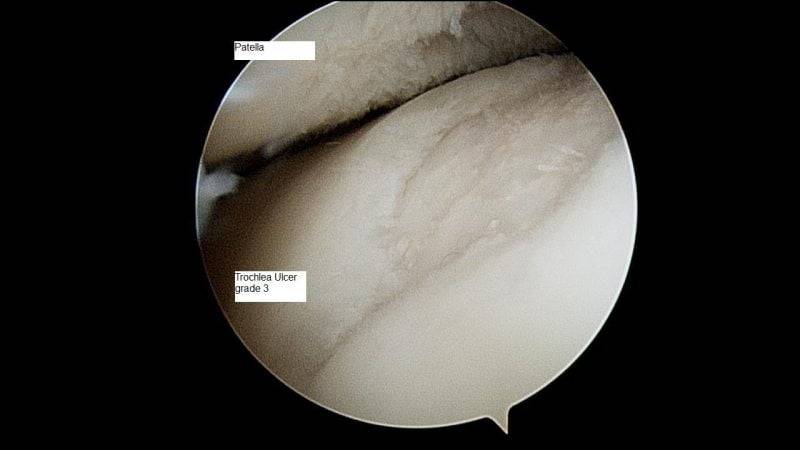

Начальная стадия артроза коварна еще и тем, что диагностировать ее сложно даже профессионалам и с применением аппаратных исследований. Рентгенография мало информативна: распознать заболевание по снимкам удается редко, только по уменьшению межсуставного зазора. Больше данных предоставляют артроскопия (введение инструмента для обследования в сочленение через микроразрез) и биохимический анализ взятой из сустава жидкости.